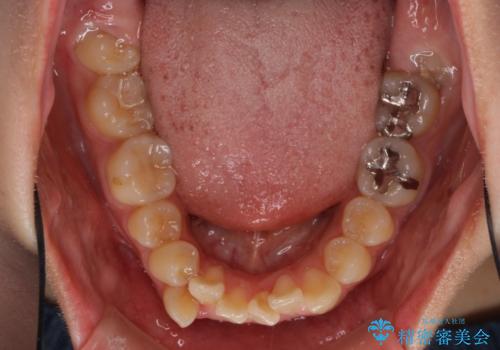

- 上下の八重歯を気にして来院された患者様です。

上下ともに八重歯の後ろの歯を1歯ずつ抜歯し、補助装置(リンガルアーチ)を用いて八重歯の位置を改善し、その後インビザラインにより矯正治療を行うこととしました。